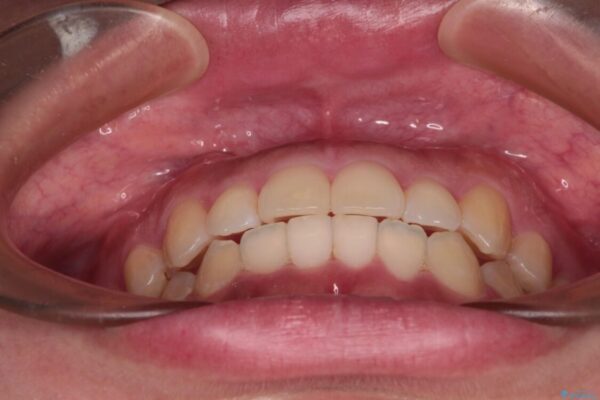

カリエールディスタライザーを併用したことで、すっきりとした口元になり、上下の正中を合わせることができました。

治療後

• 【モニター】カリエール・ディスタライザーを併用した八重歯のインビザライン矯正 治療後画像